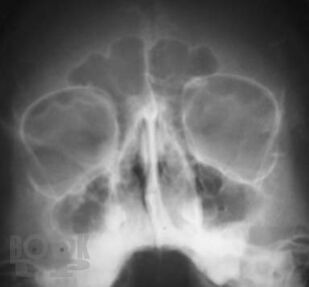

Рентгенографическая и компьютерно-томографическая диагностика острых и хронических синуситов

Монография посвящена применению классической рентгенографии и рентгеновской компьютерной томографии для диагностики острых и хронических воспалительных заболеваний околоносовых пазух. Результаты обоих исследований сопоставлены между собой по разработанной авторами методике, предложены адаптированные к практической работе подходы к обоснованному выбору указанных методов рентгенодиагностики синуситов. Книга хорошо иллюстрирована, содержит примеры описания рентгенограмм и компьютерных томограмм околоносовых пазух.

Книга рассчитана на врачей-рентгенологов, в том числе работающих на рентгеновских компьютерных томографах, врачей-оториноларингологов, интернов и ординаторов кафедр лучевой диагностики.